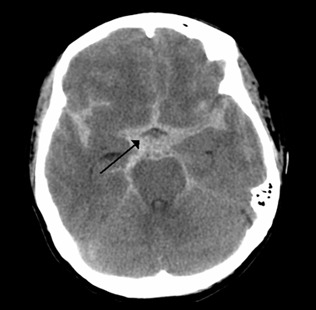

지주막하출혈은 발병 후 3시간 이내가 생존율과 예후를 결정하는 중요한 시점입니다. 출혈량과 뇌부종의 정도에 따라 환자의 상태가 급격히 악화되므로 신속한 진단과 치료가 필수적입니다.

- 정밀 검사: CT(컴퓨터 단층촬영) 및 MRI를 통해 출혈 부위와 정도를 확인합니다.